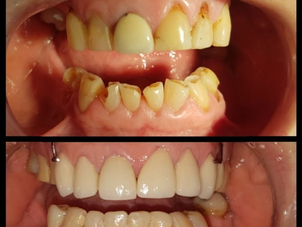

Otra buena práctica es solicitar al médico fotos del antes y después de algunos de sus pacientes con patologías similares para corroborar la tasa de éxito y de los resultados del tratamiento.

Antes y Después Clínica Dental Exceldent Plus